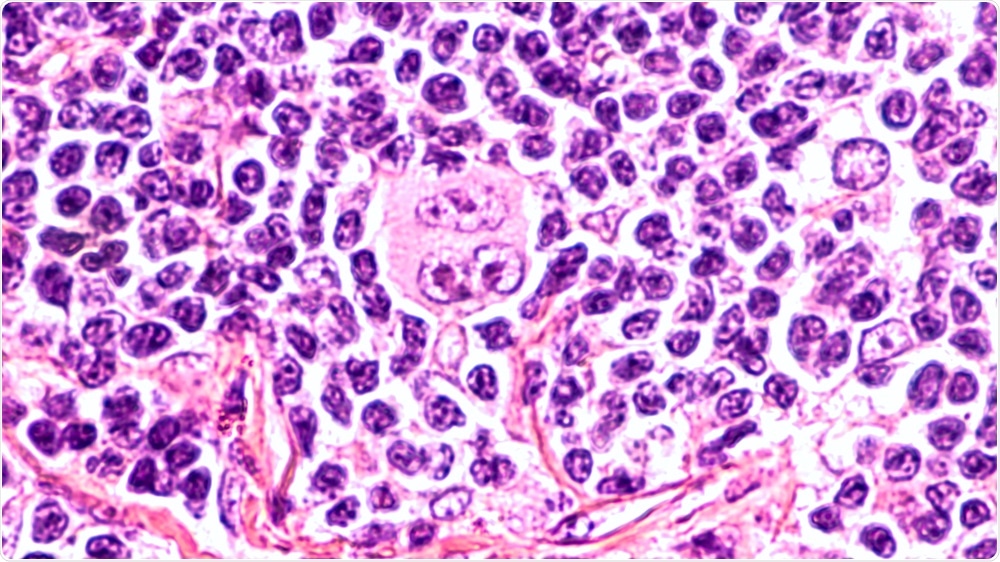

Image Credit: David. A. Litman/Shutterstock.com

The present study specifically looked at the analysis of Hodgkin lymphoma tissue, systematically exploring tumor cell properties as well as their spatial neighborhood relations. To do this, the team studied over 400,000 immunohistochemically stained whole slide images of tissue samples taken from cases of classical Hodgkin lymphoma, nodular sclerosis, and mixed cellularity, and lymphadenitis (inflammation of the lymph nodes).

The researchers believe that these key differences could help distinguish between Hodgkin lymph nodes containing tumor cells, and inflamed lymph nodes, two scenarios that can look similar under the microscope. The findings showed that CD30-positive cells in the microenvironment are different in different diagnoses.